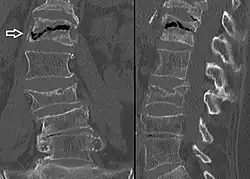

A compression fracture is a collapse of a vertebra. It may be due to trauma or due to a weakening of the vertebra (compare with burst fracture). This weakening is seen in patients with osteoporosis or osteogenesis imperfecta, lytic lesions from metastatic or primary tumors,[1] or infection.[2] In healthy patients, it is most often seen in individuals suffering extreme vertical shocks, such as ejecting from an ejection seat. Seen in lateral views in plain x-ray films, compression fractures of the spine characteristically appear as wedge deformities, with greater loss of height anteriorly than posteriorly and intact pedicles in the anteroposterior view.[3]

Compression fractures are usually diagnosed on spinal radiographs, where a wedge-shaped vertebra may be visible or there may be loss of height of the vertebra. In addition, bone density measurement may be performed to evaluate for osteoporosis. When a tumor is suspected as the underlying cause, or the fracture was caused by severe trauma, CT or MRI scans may be performed.